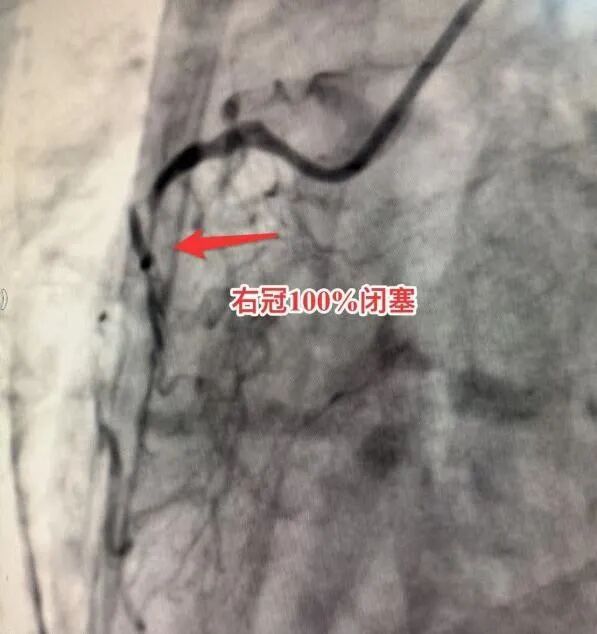

死里逃生后的康先生终于接受了冠脉造影检查。结果令人震惊:实际冠脉病变程度比CTA显示的还要严重。前降支近段95%狭窄,而回旋近段和右冠中段更是完全闭塞,如同两颗沉默的炸弹。